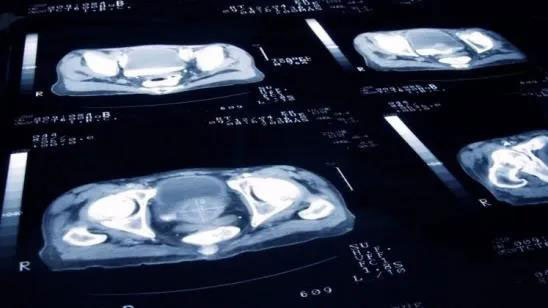

此外,還可以通過CT、MRI掃描和骨掃描來檢查是否存在前列腺癌,但這些方法在檢測前列腺癌病變方面存在局限性。

Pylarify是一款靶向前列腺特異性膜抗原(PSMA)的放射性氟化小分子顯影劑。PSMA是一種在90%以上的原發(fā)性和轉移性前列腺癌細胞表面上過度表達的蛋白,能夠顯示淋巴結、骨和軟組織轉移,以確定是否復發(fā)和/或轉移前列腺癌。

Pylarify PET結合了PET成像的準確性、PSMA靶向的精確性和F18放射性同位素的清晰度,如同擁有了“火眼金睛”,具備了更加精準的診斷性能。